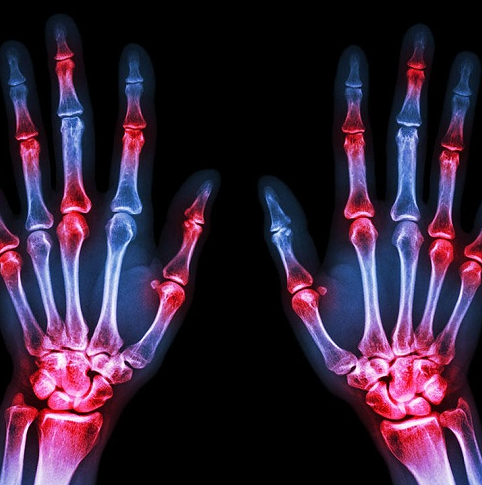

Một số bệnh tự miễn bao gồm lupus ban đỏ hệ thống và viêm khớp dạng thấp xảy ra khi hệ miễn dịch của cơ thể quay lại tự tấn công các mô bình thường khỏe mạnh. Theo tạp chí Journal of Clinical Medicine Research, hiện tượng này cũng gây ra các chứng viêm mãn tính mà có thể dẫn tới tình trạng xơ cứng mạch máu và các bệnh tim mạch khác. Do vậy, trong trường hợp đang mắc phải bệnh tự miễn, hãy hợp tác với bác sỹ để đảm bảo rằng bạn đang điều trị đúng hướng – bao gồm cả những biện pháp theo dõi sức khỏe tim mạch.